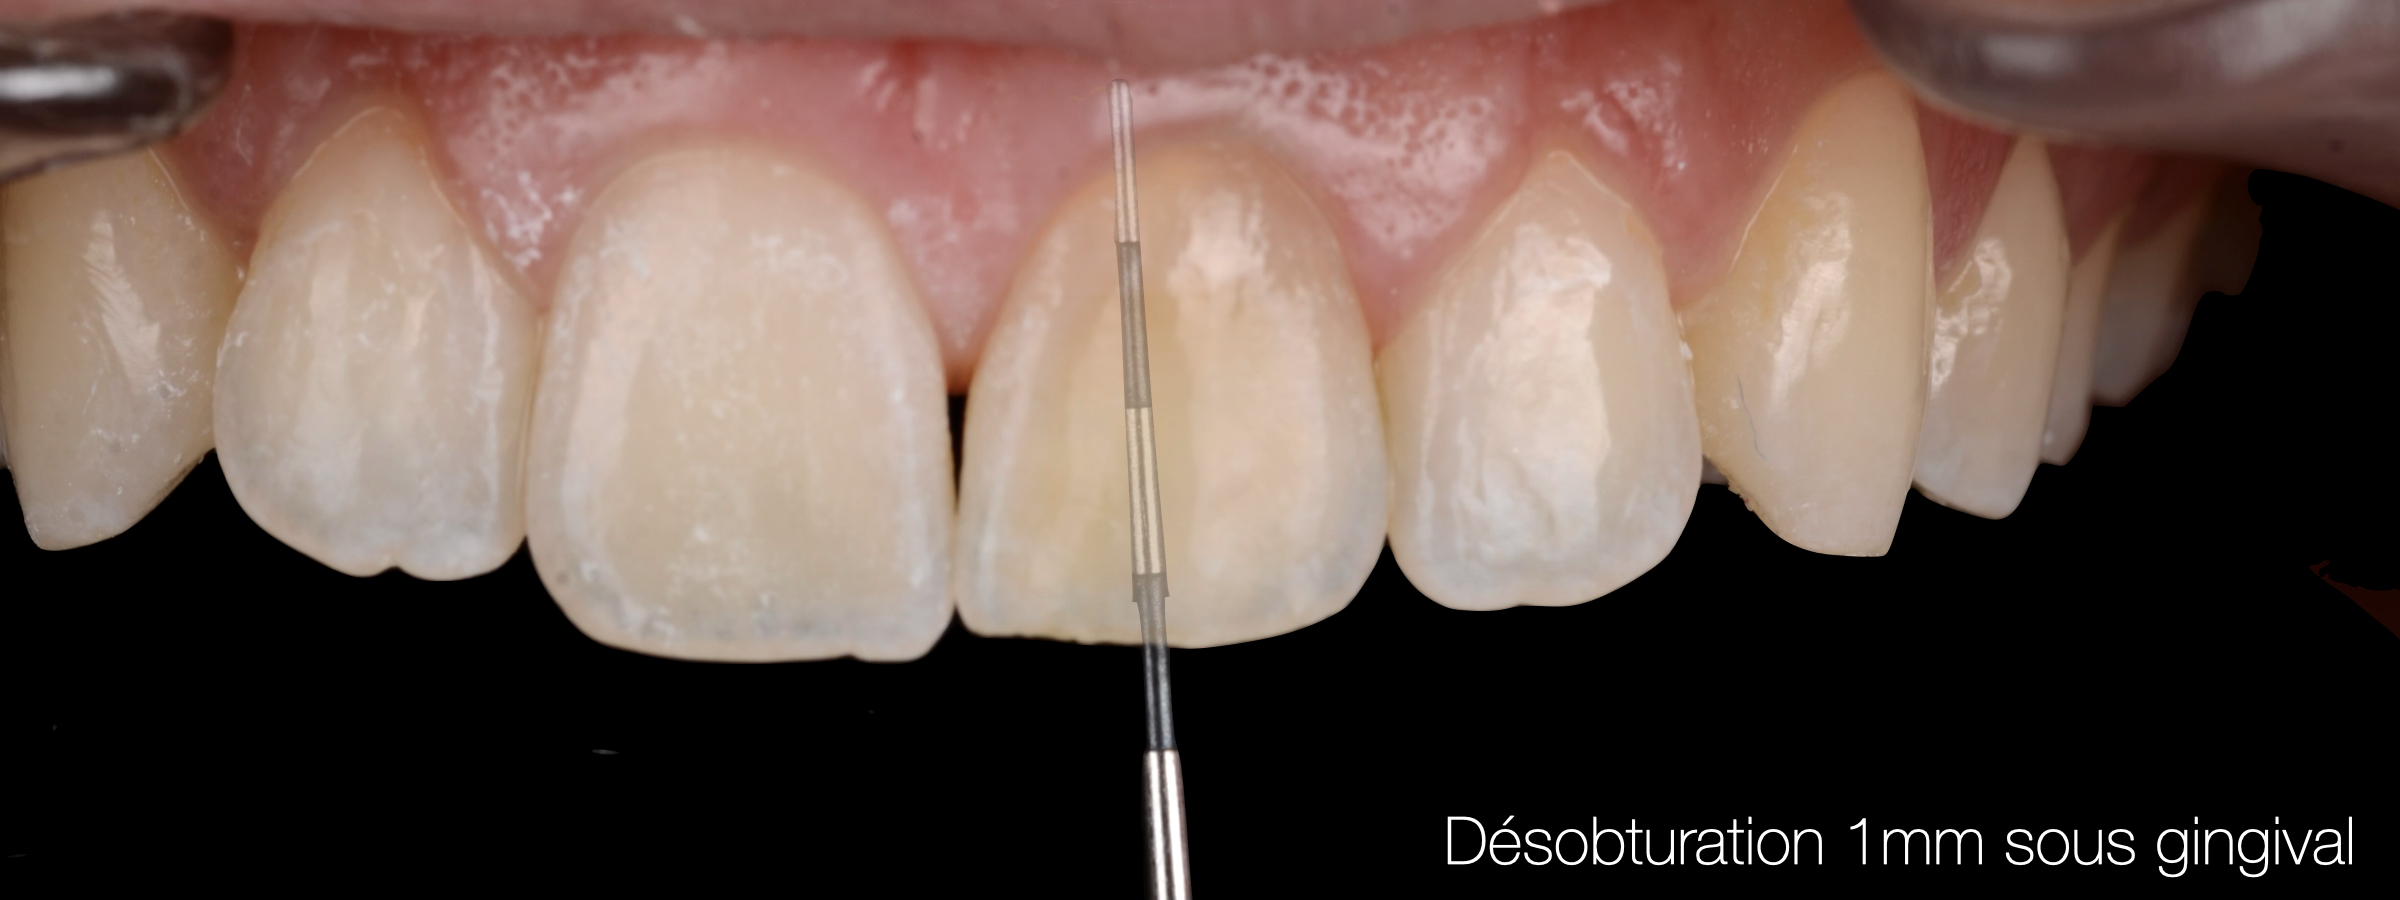

La couronne clinique est mesurée à l’aide d’une sonde parodontale jusqu’au collet puis cette mesure est reportée dans la cavité pour désobturer la gutta 1 mm sous le niveau cervical visible.

Fig. 07 : mesure de la couronne clinique à l’aide d’une sonde parodontale.

Fig. 08 : désobturation 1mm sous gingival.